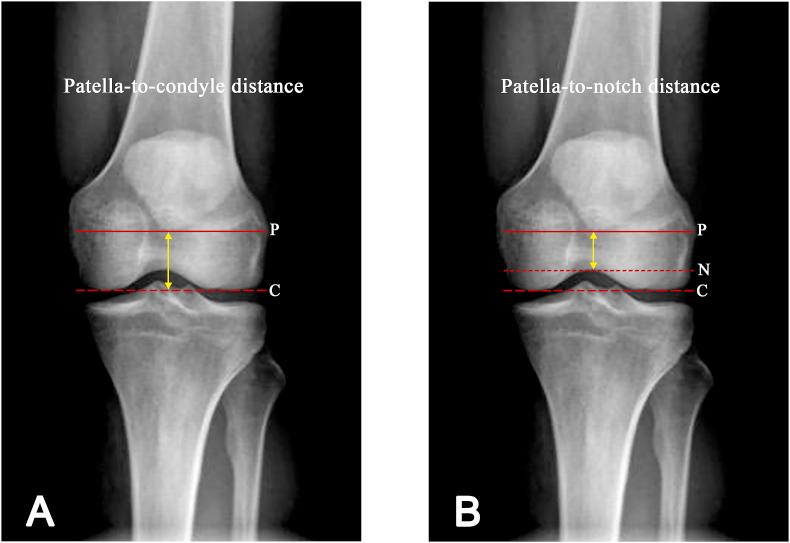

BACKGROUND/OBJECTIVE: Graft-tunnel length mismatch is a common intraoperative technical problem for anterior cruciate ligament reconstruction (ACLR) using a bone-patellar tendon-bone graft (BPTB). The patella-to-condyle and the patella-to-notch distances are two measurements in an anteroposterior knee radiograph. The objective of this study was to evaluate the sensitivities, specificities and reliabilities of those 2 measurements for detecting patients who had a patellar tendon length exceeding 45 mm.

One hundred and twenty-seven patients with an average age of 29.5 years old were evaluated. The mean patellar tendon length was 41.3 ± 5.0 mm. Patients with a length more than 45 mm (20 patients, 16%) had significantly higher patella-to-condyle and patella-to-notch distances, and more frequent use of bone staples for distal graft fixation than patients with a length ≤ 45 mm. To detect patients with a patellar tendon length over 45 mm, the optimal cutoff point for the patella-to-condyle distance was set at 14.5 mm, which had a sensitivity of 80%, specificity of 71%, and AUC of 0.76. In the case of the patella-to-notch distance, the cutoff point of 5.5 mm had a sensitivity of 80%, specificity of 66%, and AUC of 0.73. The intra- and inter-rater reliabilities of the two measurements were excellent, with ICCs of over 0.90.

Preoperative measurements of the patella-to-condyle and the patella-to-notch distances in AP knee radiographs can be valuable tools, with good sensitivities and specificities, for the determination of the patellar tendon length when using a BPTB graft for an ACLR. They had an acceptable level of discrimination capability and excellent reliability.